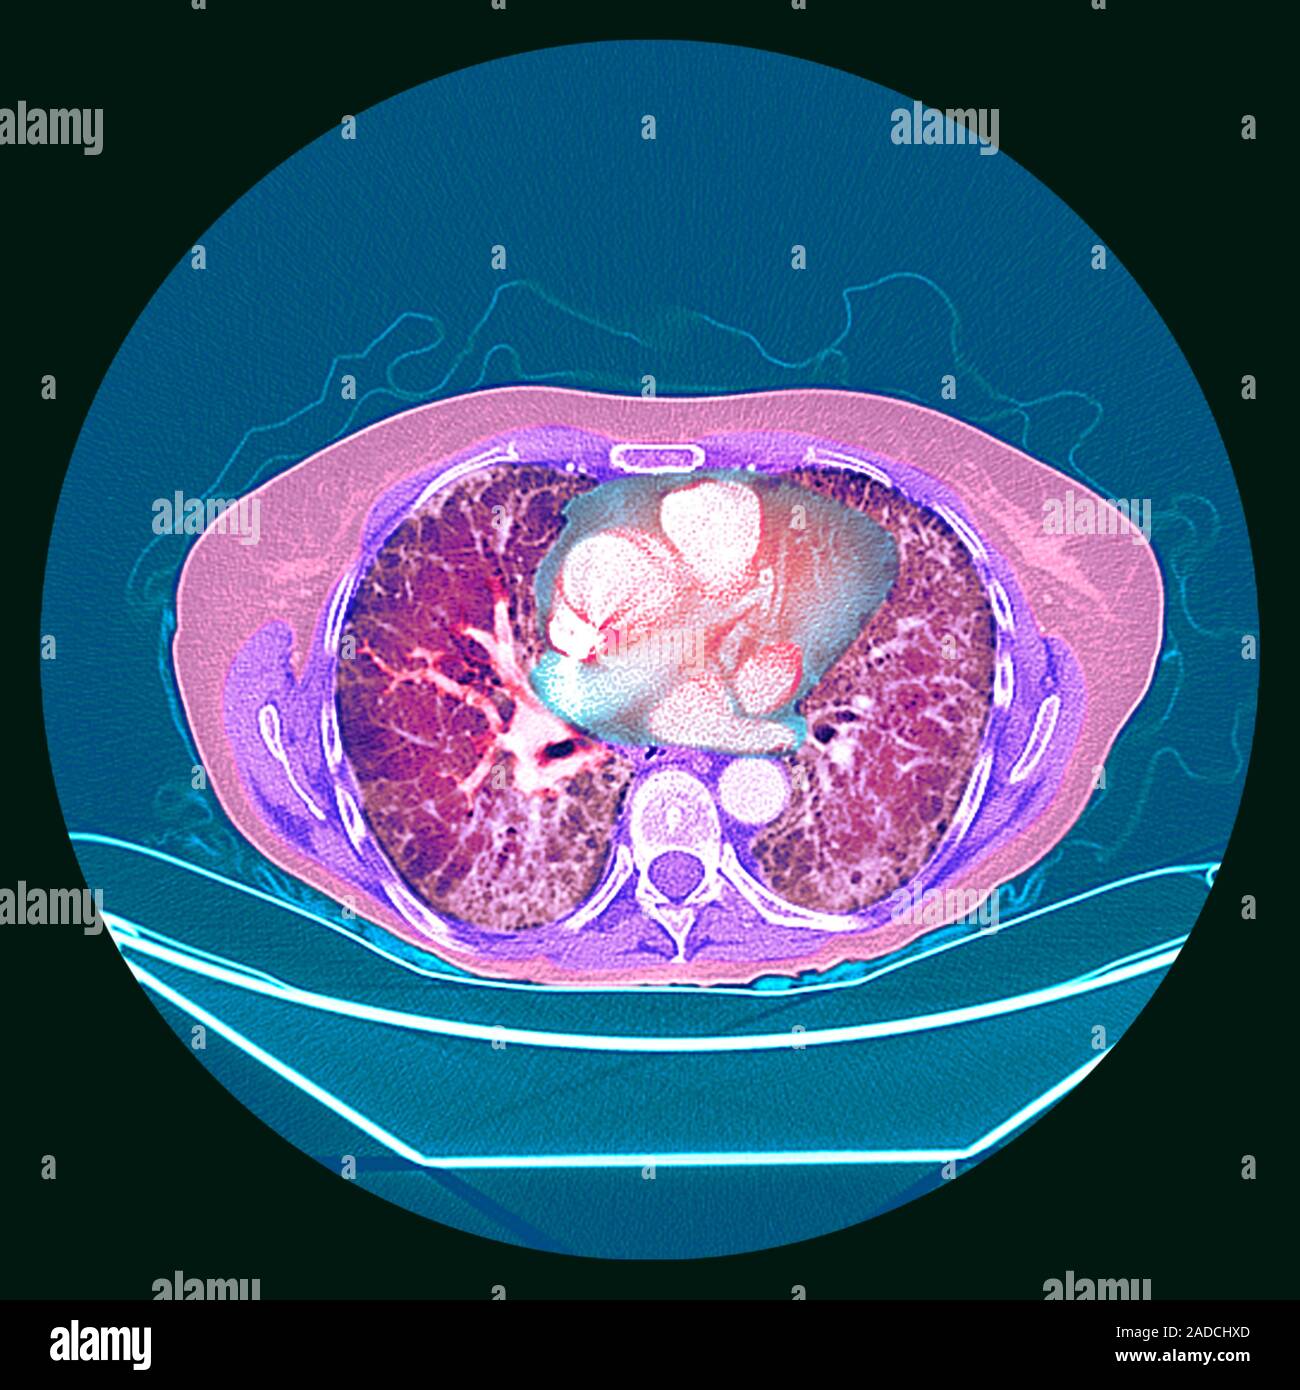

From www.alamy.com

Pulmonary fibrosis. Coloured axial computed tomography (CT) scan of the chest of a 65yearold Lung Scarring Treatment Pulmonary Fibrosis It can occur due to certain health. Doctors refer to lung scarring as “pulmonary fibrosis”. Treatment is aimed at preventing more lung scarring, managing symptoms, and helping you stay active and healthy. Treatments may slow down scarring and help. Using a mouse model, they simulated ipf by administering bleomycin, a chemotherapy agent that causes cell injury and confirmed that the. Lung Scarring Treatment Pulmonary Fibrosis.

Pulmonary fibrosis. Coloured xray showing the lungs of a 65yearold woman with pulmonary Lung Scarring Treatment Pulmonary Fibrosis Treatment for pulmonary fibrosis is aimed at slowing the course of the disease, relieving symptoms and helping you stay active and healthy. Pulmonary fibrosis is a serious lung disease that causes lung scarring and shortness of breath. Pulmonary fibrosis is scarring and thickening of the tissue around and between the air sacs called alveoli in the lungs. These changes make. Lung Scarring Treatment Pulmonary Fibrosis.